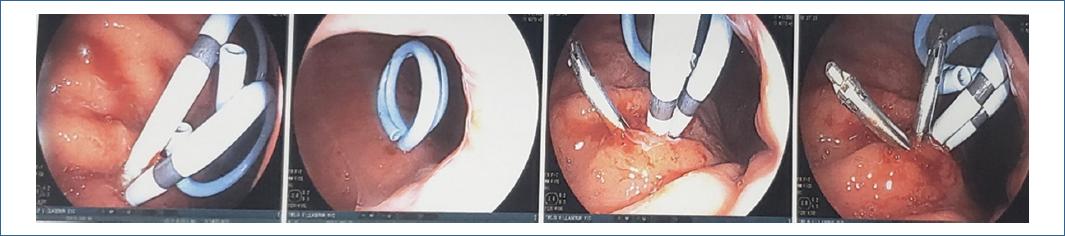

Visión endoscópica: Dilatación con balón del orificio de la cistogastrostomía, prótesis doble pigtailed in situ. La permeabilidad de la comunicación (cistogastrostomía) y drenaje se mantiene mediante la colocación de varias prótesis plásticas (Doble pigtailed). La naturaleza y la cantidad del contenido del pseudoquiste determinan el número de prótesis. Los grandes pseudoquistes con la presencia de detritos deben ser drenados con por lo menos con 3 prótesis (10 F). La presencia de detritos sólidos en grandes pseudoquistes puede beneficiarse de la colocación de una sonda nasoquística, junto con las prótesis de doble pigtail. La irrigación continua o intermitente con solución salina ayuda a evacuar los detritos y evitaría la infección del pseudoquiste. Tras algunos días de lavado a través de la sonda, esta se puede retirar con apoyo de fluoroscopia, dejando solo las prótesis in situ.